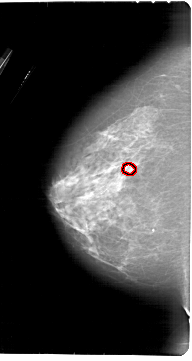

A_1913_1.LEFT_CC

LEFT_CC LINES 6841 PIXELS_PER_LINE 3646 BITS_PER_PIXEL 12 RESOLUTION 43.5 OVERLAY

FILE: A_1913_1.LEFT_CC.OVERLAY

TOTAL_ABNORMALITIES 1

ABNORMALITY 1

LESION_TYPE CALCIFICATION TYPE PLEOMORPHIC DISTRIBUTION CLUSTERED

ASSESSMENT 4

SUBTLETY 4

PATHOLOGY BENIGN

TOTAL_OUTLINES 1